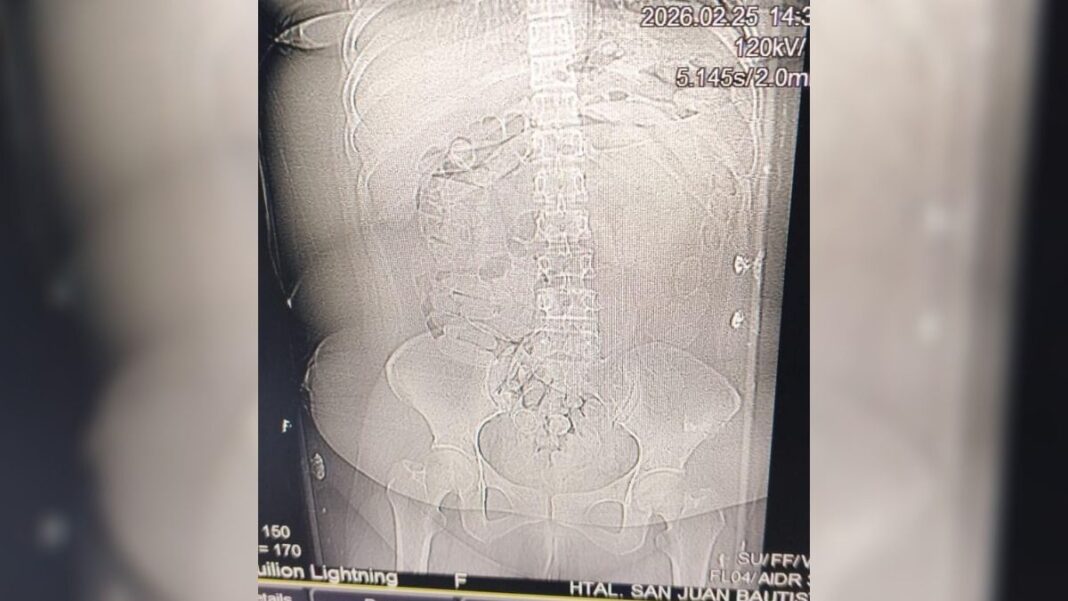

Tras los estudios correspondientes, se constató la presencia de cuerpos extraños en la zona abdominal y en la cavidad genital. Como resultado del seguimiento médico, se confirmó la evacuación de 90 cápsulas.

La sustancia contenida en los envoltorios era de color blancuzco y, al ser sometida a la prueba de campo Narcotest, arrojó resultado positivo para cocaína, con un peso total de 1 kilo 069 gramos.